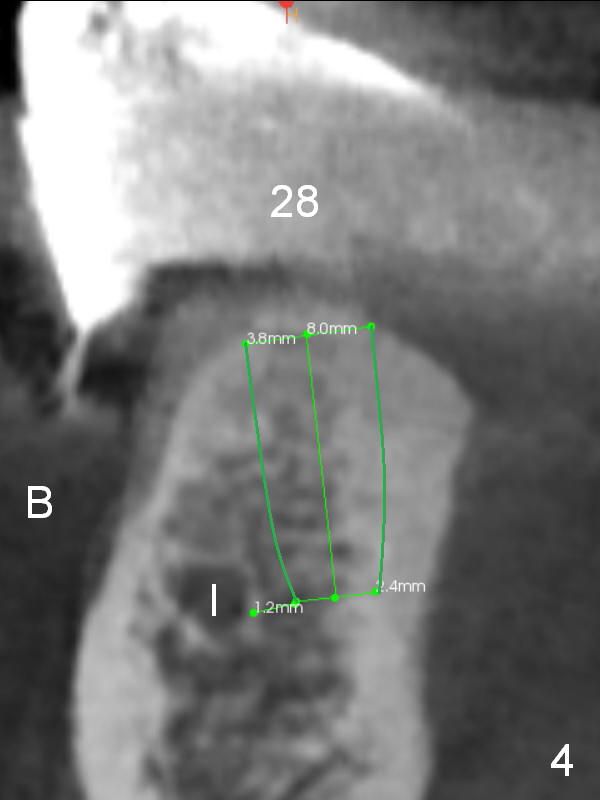

The patient wants to change unstable complete dentures to fixed ones.  Because the problem of pain is associated with the lower left (Fig.1 the left Inferior Alveolar Nerve is more superficial), the lower arch will be reconstructed first.  Totally 6 implants will be placed for bridges/crowns.  Due to time constraint, four implants are placed at the 1st stage (#21, 22, 27 and 28 (Fig.4,5,8,9)); the lower denture will be retained immediately by ball abutments and soft relined.  Two to three months later, two more implants will be placed (at #31 and 20, Fig.2,10).  Note severe atrophy of the crest at #18 and 19 (Fig.11 and 12).  If primary stability is achieved, a fixed immediate provisional will be fabricated.

In contrast to the upper arch, the bone density in the lower arch is high.  The challenge is bone height.  Short implants will be used (6 mm for #31 (Fig.2) and 8 mm for the majority of the others (at premolar and canine sites).  If needed, extra implants will be placed at incisor sites (Fig.6,7 (implant can be longer)) and at #29 (Fig.3) .  If a site is too small for a 3.8 mm 2-piece implant, a 1-piece one may be placed.